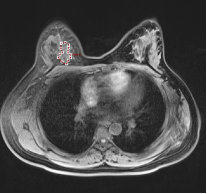

2.2 形态学特征(Form Factor Features) 本类特征主要通过数学的方法刻画病灶部位的形状,试图描述病灶部位的形状、紧致性等信息。图3.a和图3.b分别表示形态不同的两个三维病灶。假设考虑对这两个三维病灶求形态学特征,将有如下情况:

a b 图3. 不同形态的两个三维病症

VolumeCC:体积,描述病灶体积大小,若体积越大,则VolumeCC越大; Surface:表面积,描述病灶表面积大小,若表面积越大,则Surface越大; SurfaceVolumeRation:表面积体积比,描述病灶表面积与体积之比,如果三维病灶的边缘不规则程度越大,则该比值越大,说明三维肿瘤的异质性越大;假设图3.a病灶的边缘不规则程度小于图3.b,则表面积体积比可表述为SurfaceVolumeRatio& #40;3.a& #41;< SurfaceVolumeRatio & #40;3.b& #41;; Compactness:紧致性,描述了病灶的球状性程度;若病灶越像球形,则Compactness值越大;假设图3.b病灶较图3.a病灶更接近于球形,则可表述为 Compactness& #40;3.a& #41;< Compactness& #40;3.b& #41;; Maxmun3DDiameter:最大直径,描述三维病灶部位的最长直径,病灶部位的跨度越大,则Maxmun3DDiameter值越大。